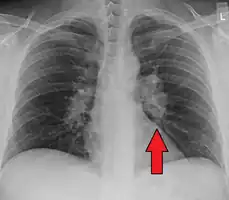

![]() | |

| Chest X-ray showing the typical nodularity of sarcoidosis, predominantly in the bases of the lungs. | |

Chest radiograph changes are divided into four stages:[96]

- bihilar lymphadenopathy

- bihilar lymphadenopathy and reticulonodular infiltrates

- bilateral pulmonary infiltrates

- fibrocystic sarcoidosis typically with upward hilar retraction, cystic and bullous changes

Although people with stage 1 radiographs tend to have the acute or subacute, reversible form of the disease, those with stages 2 and 3 often have the chronic, progressive disease; these patterns do not represent consecutive "stages" of sarcoidosis. Thus, except for epidemiologic purposes, this categorization is mostly of historic interest.[26]